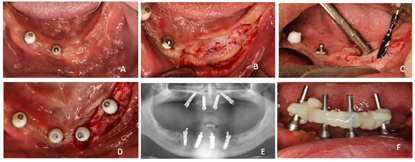

患者口腔卫生差,恒牙列,11、17、26、27、36、41、46、47缺失,11、41见树脂牙修复,牙冠形态不规则,11与21、22、23、12、13间,41与42、43、31、32间可见树脂与金属结扎丝连接固定,树脂连接体部分折裂,边缘见明显悬突。上下颌余留牙齿舌侧见大量牙石,全口牙龈萎缩,牙根暴露约1/3,牙龈局部红肿明显,探诊出血。全口余留牙齿松动Ⅲ度。口腔黏膜检查未见明显异常(图1)。

(1)种植外科一期手术

①阿替卡因肾上腺素注射液局部浸润麻醉,剪断固定结扎丝,拔除上下颌松动牙齿(图4)。暂保留了双侧下颌第三磨牙,主要考虑若下颌不能种植即刻修复情况下,利用38、48作为基牙辅助过渡可摘义齿固位。